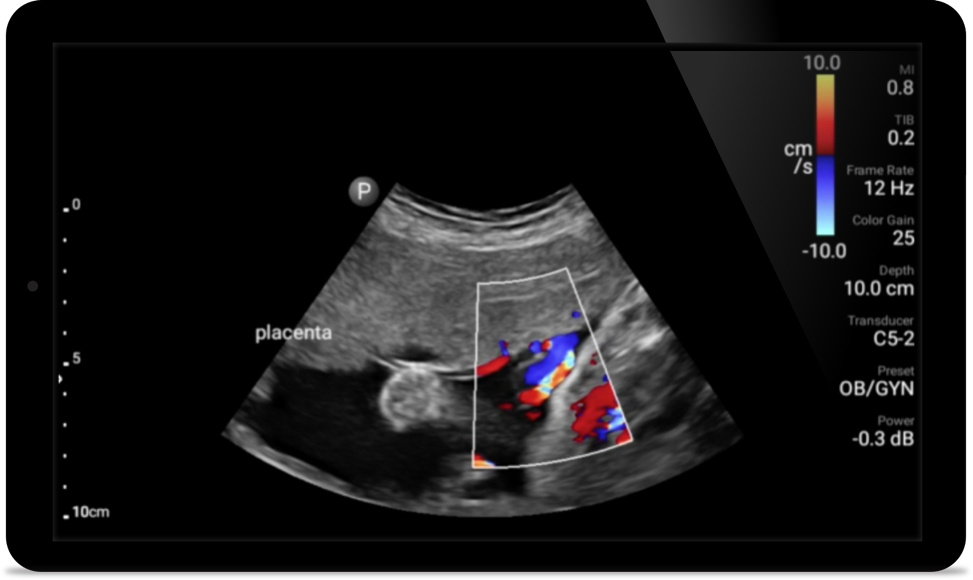

• Rango extendido de frecuencias de operación de 4 a 1 MHz • 2D, Doppler a color, Modalidad M, XRES avanzado e imágenes armónicas multivariables • Imágenes de alta resolución para aplicaciones abdominales y cardíacas: las optimizaciones de preajustes de imágenes cardíacas, gineco-obstétricas, pulmonares, abdominales y FAST de Lumify ayudan a la tecnología que salva vidas en entornos prehospitalarios

Lumify ayuda a la tecnología que salva vidas en entornos prehospitalarios